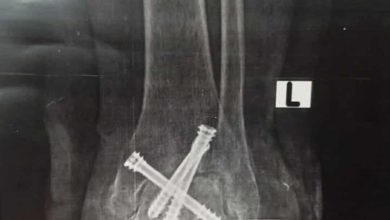

خدمات جديدة وجراحات نوعية بقسم العظام بمستشفي النيل للتأمين الصحي

كتب – محمد الهادى تحت إشراف الدكتورأحمد عبد الحفيظ مدير المستشفي، أجرت مستشفي النيل للتأمين الصحي، جراحة تثبيت لكسر معقد…